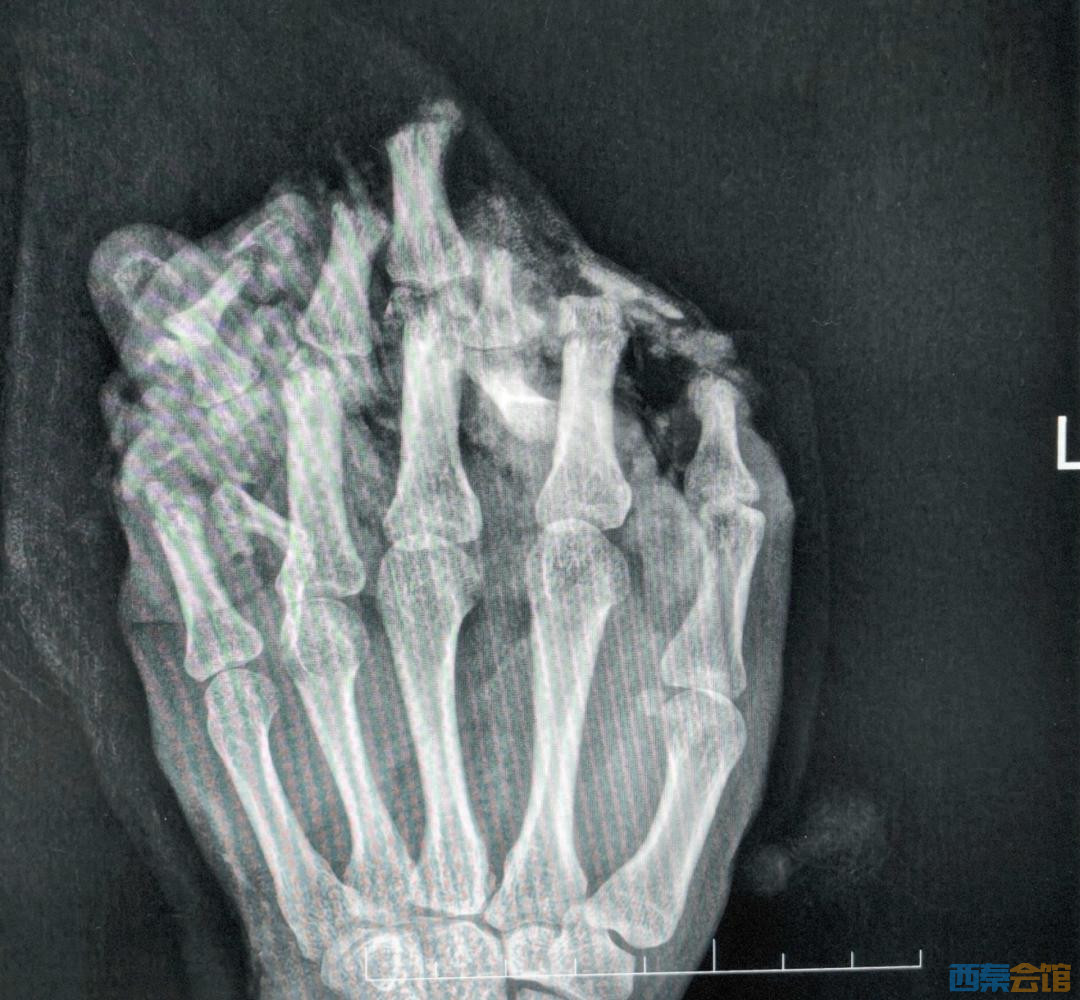

近日,广东东莞24岁的工人小王工作时,左手不慎被机器碾压,导致左手严重受伤,导致左手严重受伤,手掌、手背、各指掌侧及背侧皮肤脱套流血、疼痛,被紧急送到医院。

(拍片显示左手伤情严重)

医生诊断他为:1.左手掌、手背,示指中指环指小指掌侧及背侧皮肤毁损脱套伤;2.左手掌、手背及各指肌腱神经血管损伤;3.左手多发性开放性指骨骨折伴毁损;4.左拇指末节指腹皮肤、软组织缺损;5.左拇指指固有神经断裂;6.左拇指甲床裂伤。